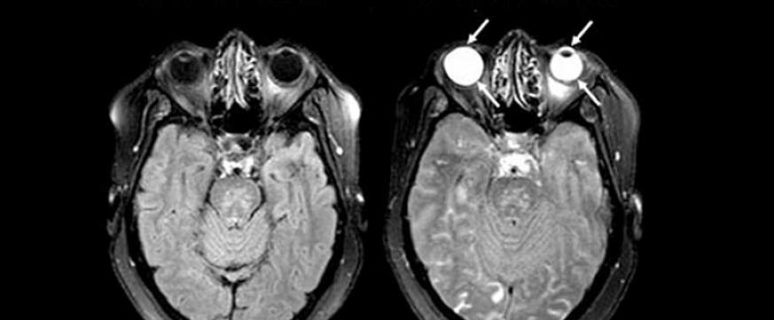

עכירות הקרנית וממאירות אצל רופאים, רנטגנאים ואחיות עובדי קרינה MRI - מושגי יסוד ופיזיקה